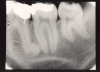

Bitewing examinations were introduced by Dr. Raper in 1925. Bitewing images focus on the clinical crowns of both the maxillary and mandibular teeth. Bitewings do not show the apices of the tooth and cannot be used to diagnose in this area. The greatest value of bitewing radio- graphic images is the detection of interproximal caries in the early stages of development, before it is clinically apparent. The arrows in Figure 2 indicate areas of interproximal caries. Bitewing images also reveal the size of the pulp chamber and the relative extent to which proximal caries have penetrated.

Figure 2 - Bitewing Images

Figure 2